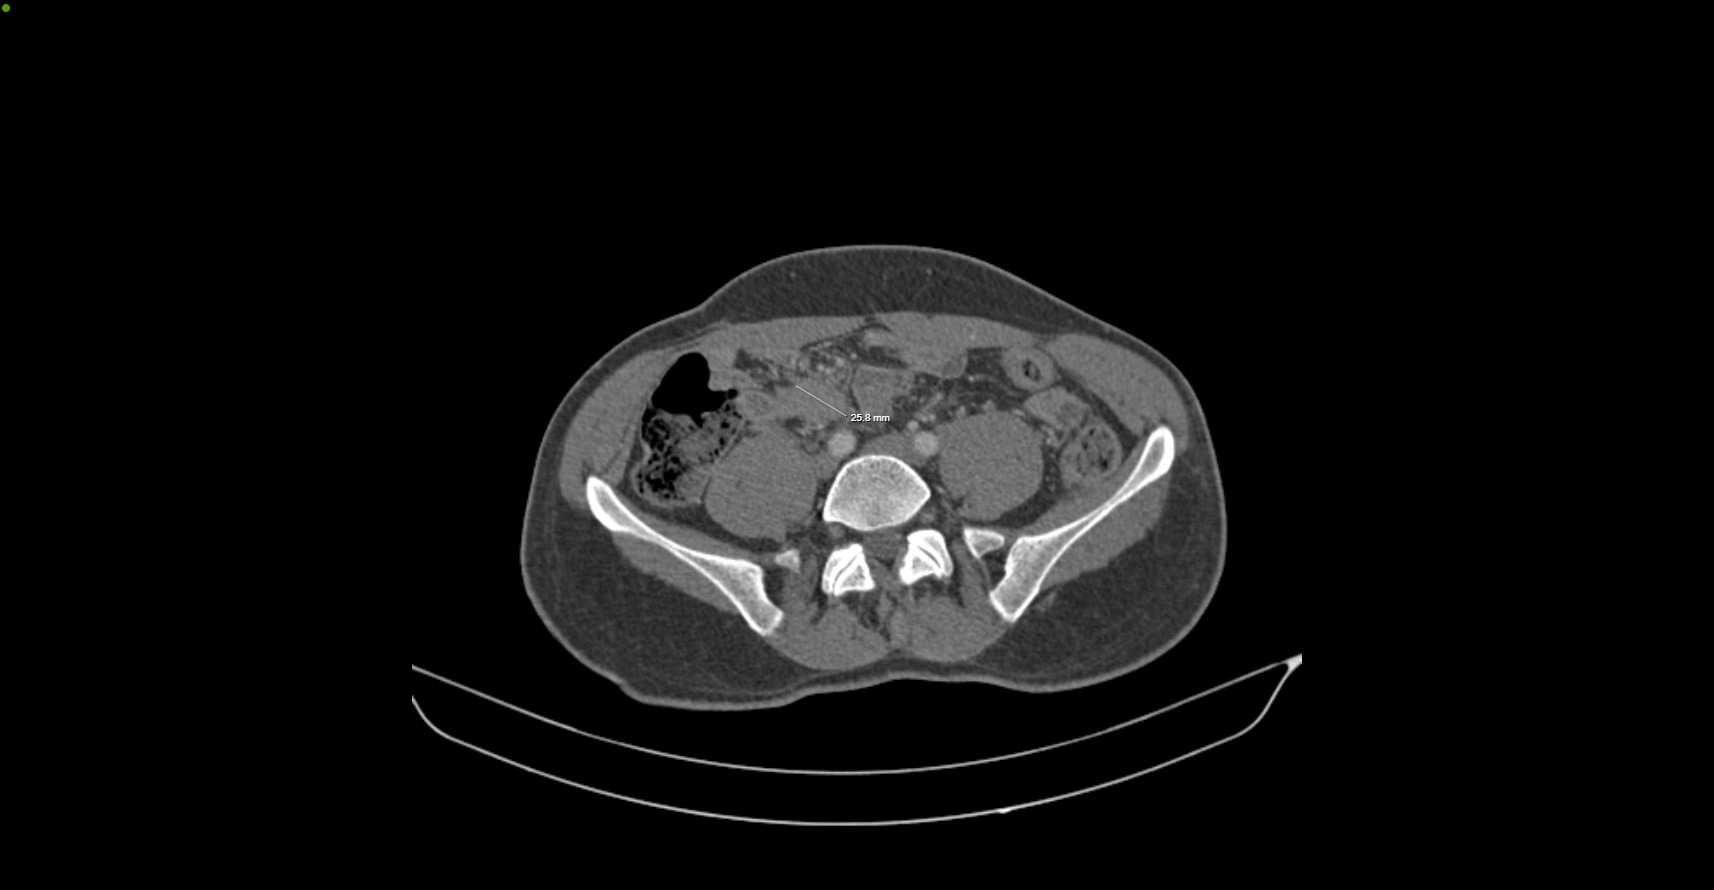

A reassessment CT scan performed on October 27, 2023 (Figures 1-4), after a year of treatment, showed partial regression of the tumor mass measuring then 30 × 18 × 34 mm.

Figure 1. Axial CT scan showing partial tumor regression (~30 mm) after 12 months of sorafenib therapy.